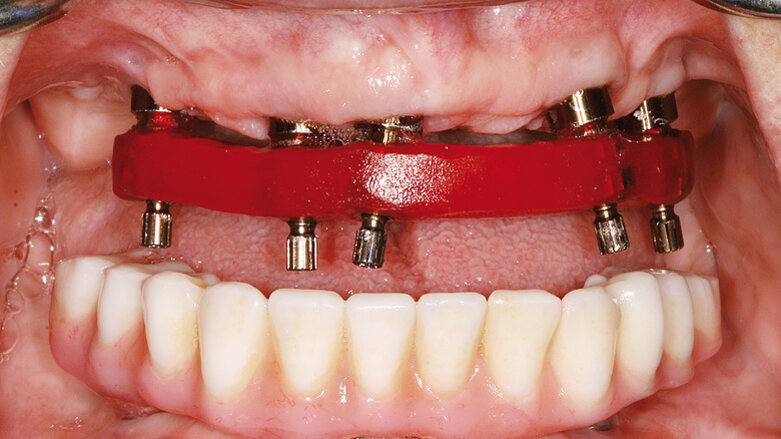

Hlavním požadavkem pacientky bylo vylepšení svého estetického vzhledu a komfortu s přáním permanentního a rychlého řešení jejího selhávajícího chrupu. Ve finálním ošetření si rovněž přála redukci gummy smile ve frontální části maxily. Dostavila se do naší ordinace ke třetí chirurgické konzultaci ohledně imediátního zatížení maxilární a mandibulární hybridní rekonstrukce prostřednictvím terapeutického konceptu Straumann® Pro Arch (šikmé zavedení distálních implantátů umožní vyhnout se anatomickým strukturám jako sinus maxillaris, foramina mentalia mandibulae). Tento terapeutický koncept zredukoval potřebu komplementárních chirurgických zákroků a množství implantátů potřebných pro zhotovení fixní hybridní rekonstrukce v rozsahu prvních molárů. Při širokém úsměvu byla zaznamenána střední až vysoká retní linie s dvojúrovňovou okluzní rovinou. Rovněž byla registrována supraokluze horních a dolních frontálních zubů (FDI: 12, 11, 21, 22 a 41–43, US: 7–10 a 25 až 27) vytvářející hluboký skus 6 mm (obr. 2). Ve vzájemném vztahu špičáků byla zaznamenána I. An-

3. Týmová diskuse finálního chirurgického a protetického terapeutického plánu pro hybridní rekonstrukce prostřednictvím kónických bone-level (BLT) implantátů Straumann® s obnovením okluze v rozsahu prvních molárů. Pro výrobu náhrad v podobě kovem vyztužených provizorií v jeden den bylo navrženo využití nepřímé techniky.

4. Koordinace chirurgické návštěvy (dr. Robert Levine) s ordinací protetického lékaře (dr. Harry Randel), zubní laboratoří (NewTech Dental Laboratory, Lensdale, PA) a se zástupcem dentální implantologické společnosti (Straumann USA, Andover, MA). Pacientka si je vědoma možné potřeby nošení jedné nebo obou náhrad během fáze hojení, pokud hodnoty primární stability implantát při inzerci nebudou adekvátní pro imediátní zatížení. To může být způsobeno kvalitou nebo kvantitou kosti nebo potřebou augmentace kosti a membrány pro řízenou kostní regeneraci (GBR) a dvoufázový postup. Toto je velmi důležité prokonzultovat se všemi pacienty, obzvláště pokud jsou plánovány pouze čtyři implantáty v maxile a distální implantát(y) může (mohou) při inzerování vykazovat nedostatečné hodnoty primární stability kvůli kvalitě či kvantitě kosti. Signifikantně zredukovat tuto eventualitu napomáhá schopnost využívat delších, kónických (BTL) a vychýlených implantátů – jako v tomto prezentovaném případu – s adekvátním množstvím bukální kosti použitelným pro plánované implantáty o průměru 4,1 mm.